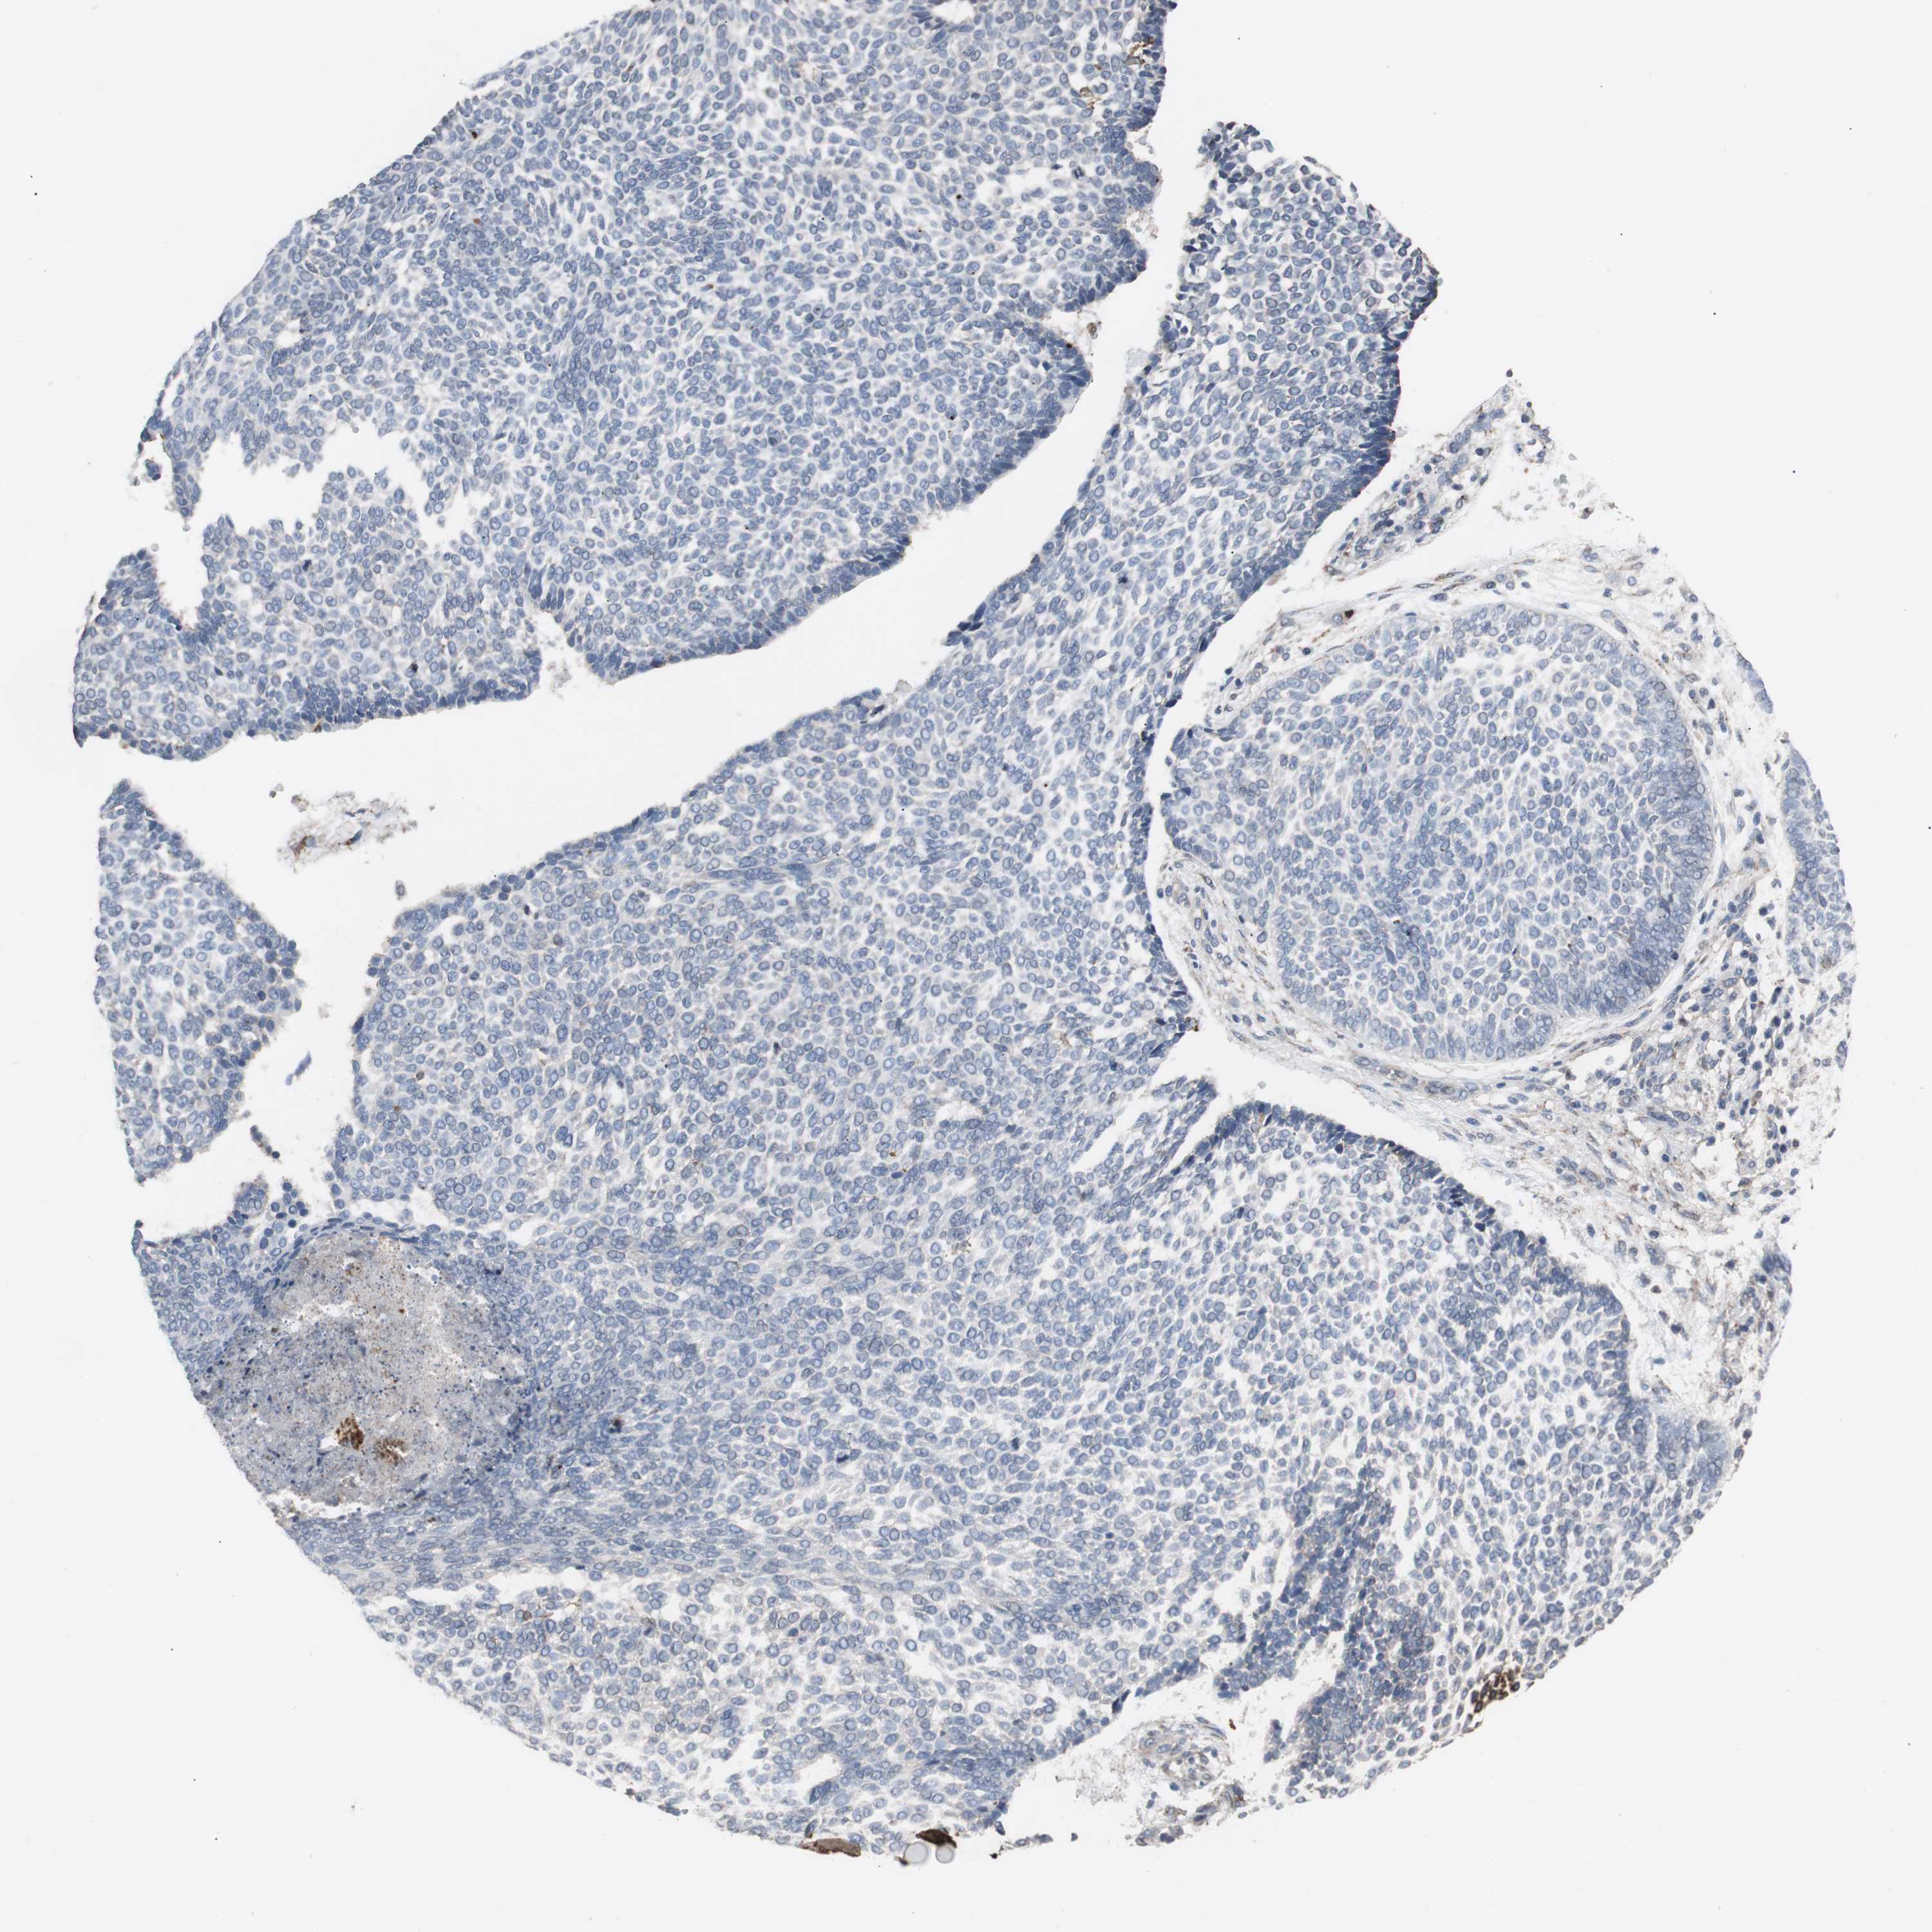

SKIN CANCER - Protein expressioni

A mouse-over function shows sample information and annotation data. Click on an image to view it in a full screen mode. Samples can be filtered based on level of antibody staining by selecting one or several of the following categories: high, medium, low and not detected. The assay and annotation is described here.

Each image is clickable and will lead to virtual microscopy that enables deeper exploration of all samples and also displays staining intensity scores, fraction scores and subcellular localization as well as patient and tissue information for each sample.

Antibody HPA006018

Staining

Not detected

Negative

<25%

None

Basal cell carcinoma